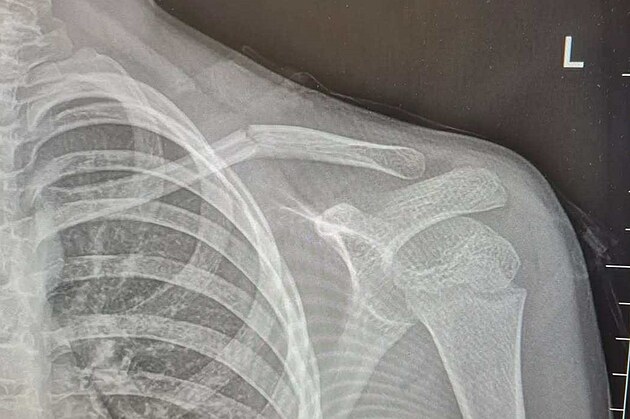

Rentgen ukazuje zlomeninu klíční kosti devítiletého chlapce.

archiv Filipa Černického